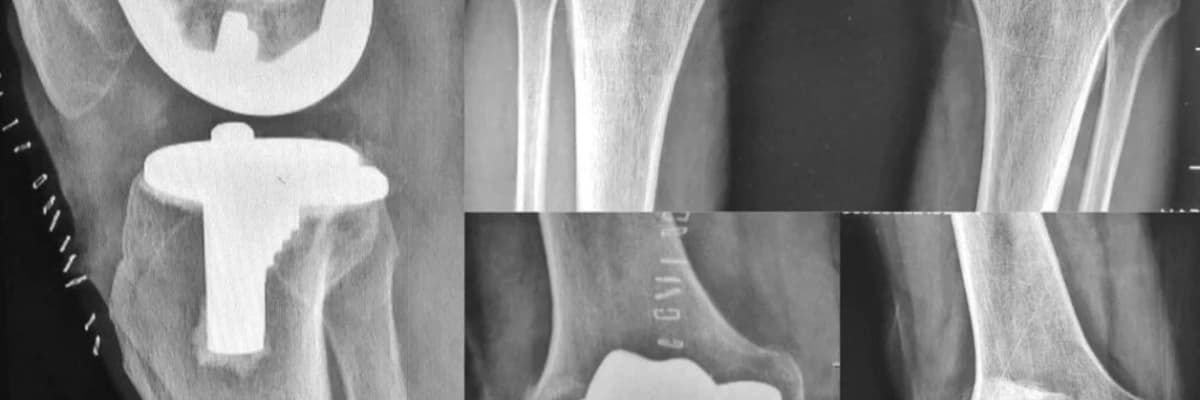

Aşınmış eklem yüzeyleri çıkartılarak yerine ağrısız ve işlevsel bir yapay eklem oluşturulur. Bu yöntem, teknolojideki ilerlemelere paralel olarak gelişmiş ve günümüzde çok başarılı bir tedavi yöntemi olarak yeini amıştır.